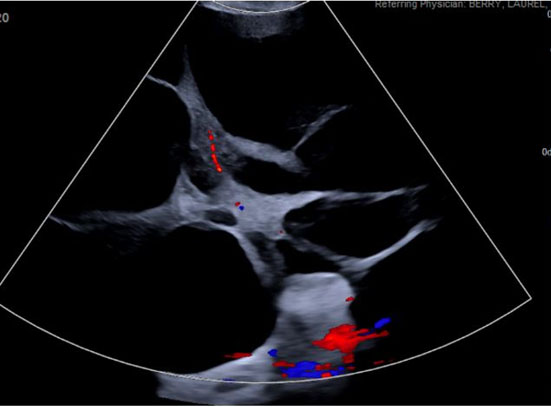

She had an uncomplicated immediate postpartum course and was discharged postpartum day 4 with plan for outpatient follow-up. Serum creatinine was normal at 0.64 mg/dL and urine protein/creatinine ratio was elevated at 0.343. She was discharged with a three day course of Lasix for lower extremity edema but was normotensive at the time of discharge with no anti-hypertensive therapy. Ultimately, she presented to another tertiary hospital emergency department (ED) roughly six weeks postpartum with worsening abdominal pain and abdominal distention. At this encounter, she was again normotensive not on anti-hypertensive therapy with urine protein 20 mg/dL on urinalysis. Transvaginal ultrasound (TVUS) demonstrated large multi-septated cystic mass filling abdomen and pelvis, measuring 35.2 × 31.2 × 16.3 cm (Figure 2). Repeat computed tomography (CT) at that time demonstrated enlargement of bilateral adnexal masses to “large multi-septated cystic mass (vs two large adjacent multi-cystic masses) nearly replacing the entire abdomen and pelvis, measuring 25.1 × 32.1 × 35.7 cm” (Figure 3). She was referred outpatient to Gynecologic Oncology and ultimately underwent exploratory laparotomy, drainage of adnexal masses, bilateral ovarian cystectomy, and reconstruction. She had large, thin walled, multi-septated cysts from both ovaries taking up the entire abdomen and pelvis. Twelve liters of serous appearing fluid was drained intraoperatively and approximately 50–100 cysts were drained individually. Pathology intraoperatively was benign and final pathology demonstrated benign ovarian cysts with features of HL.

Figure 2: Transvaginal ultrasound obtained six weeks postpartum with classic “spoke-on-wheel” appearance of cysts.

While the differential of a pelvic mass in pregnancy should remain broad and should include ruling out neoplasm, HL can be a cause of adnexal masses in pregnancy. The characteristic “spoke-on-a-wheel” appearance on ultrasound is one way to differentiate this diagnosis from other causes of adnexal mass [13]. While there are some case reports of HL first being diagnosed in the postpartum period, it is most commonly found during the third trimester or incidentally at time of caesarean section [14],[15],[16]. There are also several case reports of first and second trimester diagnoses of HL [15]. In our literature review, our case presents the first case of enlarging adnexal masses related to HL after delivery. Yang et al. report a case of HL diagnosed in the postpartum period; however, they do not have any pre-delivery imaging to compare to [17]. In their case, the patient had smaller bilateral cysts (11 and 14 cm) which were managed conservatively with resolution of the cysts three months postpartum [17].